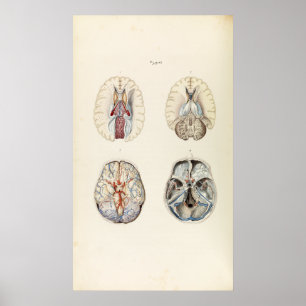

Impressão da anatomia 1880 do cérebro humano do

Preço23,90 €

Impressão

Preço23,90 €